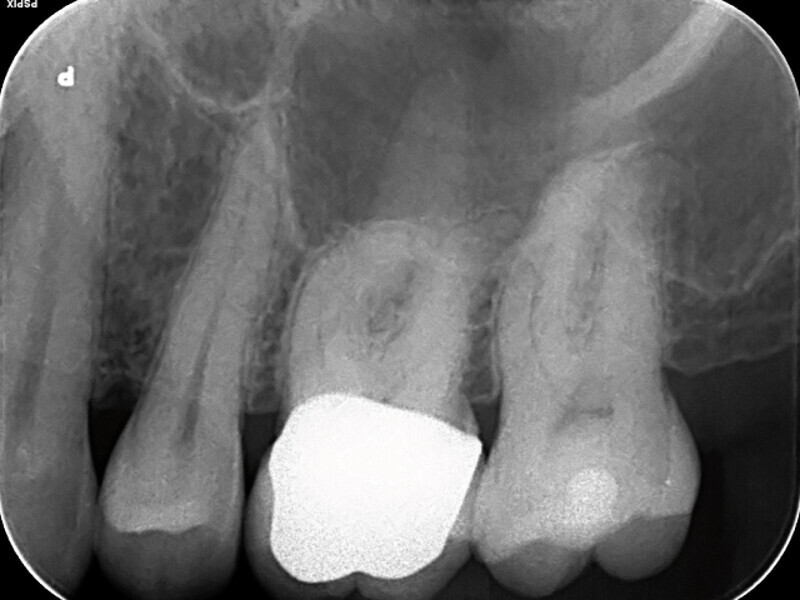

Endodontické ošetření – případová studie